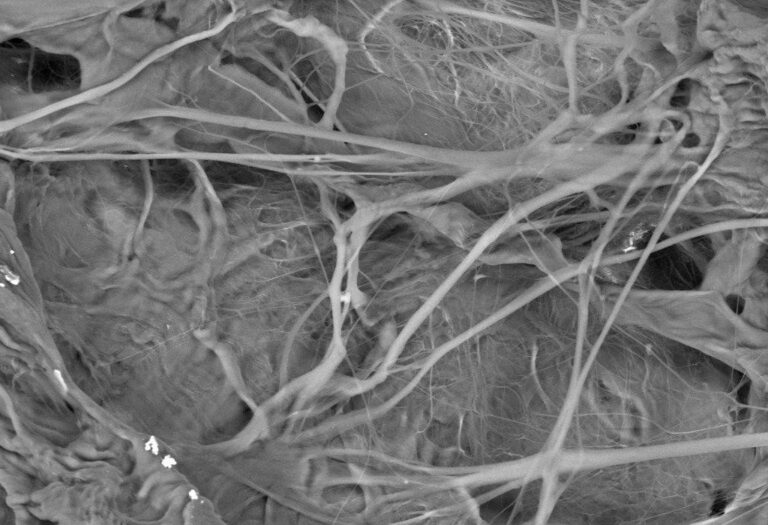

Elektron Mikroskobu (SEM) görüntüleri

SHELTER® SLOW - cross-section, 100µm

SHELTER® SLOW - cross-section, 20µm

SHELTER® SLOW - plane, 10µm